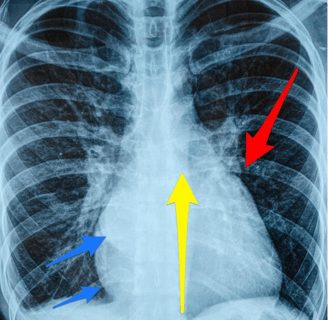

Insuficiência Cardíaca Congestiva (ICC):

Condição na qual o coração não consegue bombear sangue suficiente para atender às necessidades do corpo. Pode resultar em acúmulo de fluido nos pulmões e nos tecidos, causando dificuldade respiratória e inchaço.